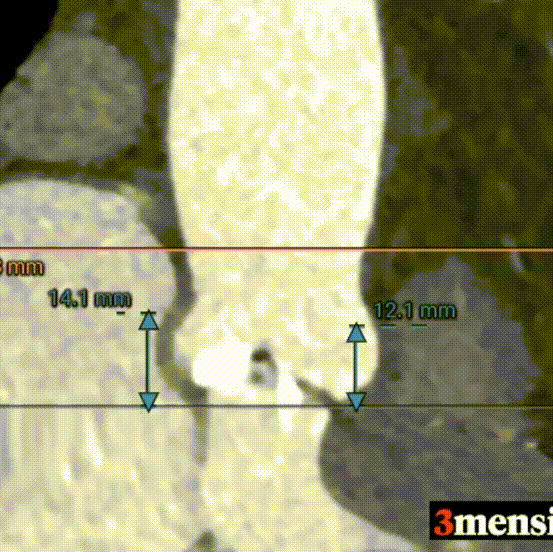

三叶式主动脉瓣;瓣环周长23mm,平均周长径72.1mm;左冠脉开口高度大于瓣叶长度;综合考虑冠脉风险低;LVOT周长径22.6mm;升主动脉直径32.1mm。

左冠高度12.1mm,右冠高度14.1mm;右冠脉开口高度大于瓣叶长度;SOV瓦式窦:平均周长径31.3mm;术中球囊预扩须密切注意冠脉灌注;STJ周长径26.5mm。